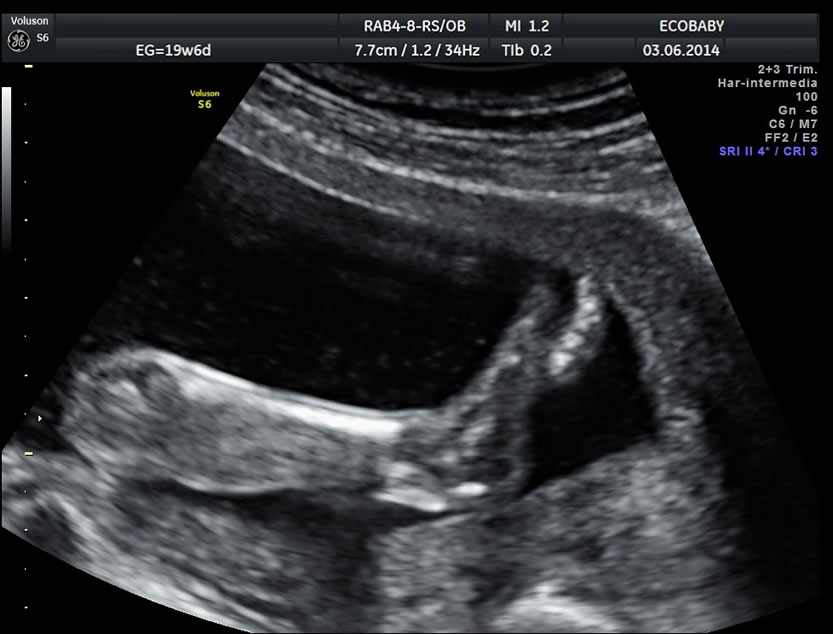

Cerebro, cuello, cara, tórax, corazón (diferentes cortes que muestran las cavidades y la correcta entrada y salida de arterias y venas), abdomen (normalidad de la pared, estómago, intestino, riñones, vejiga), miembros inferiores y superiores y columna vertebral.